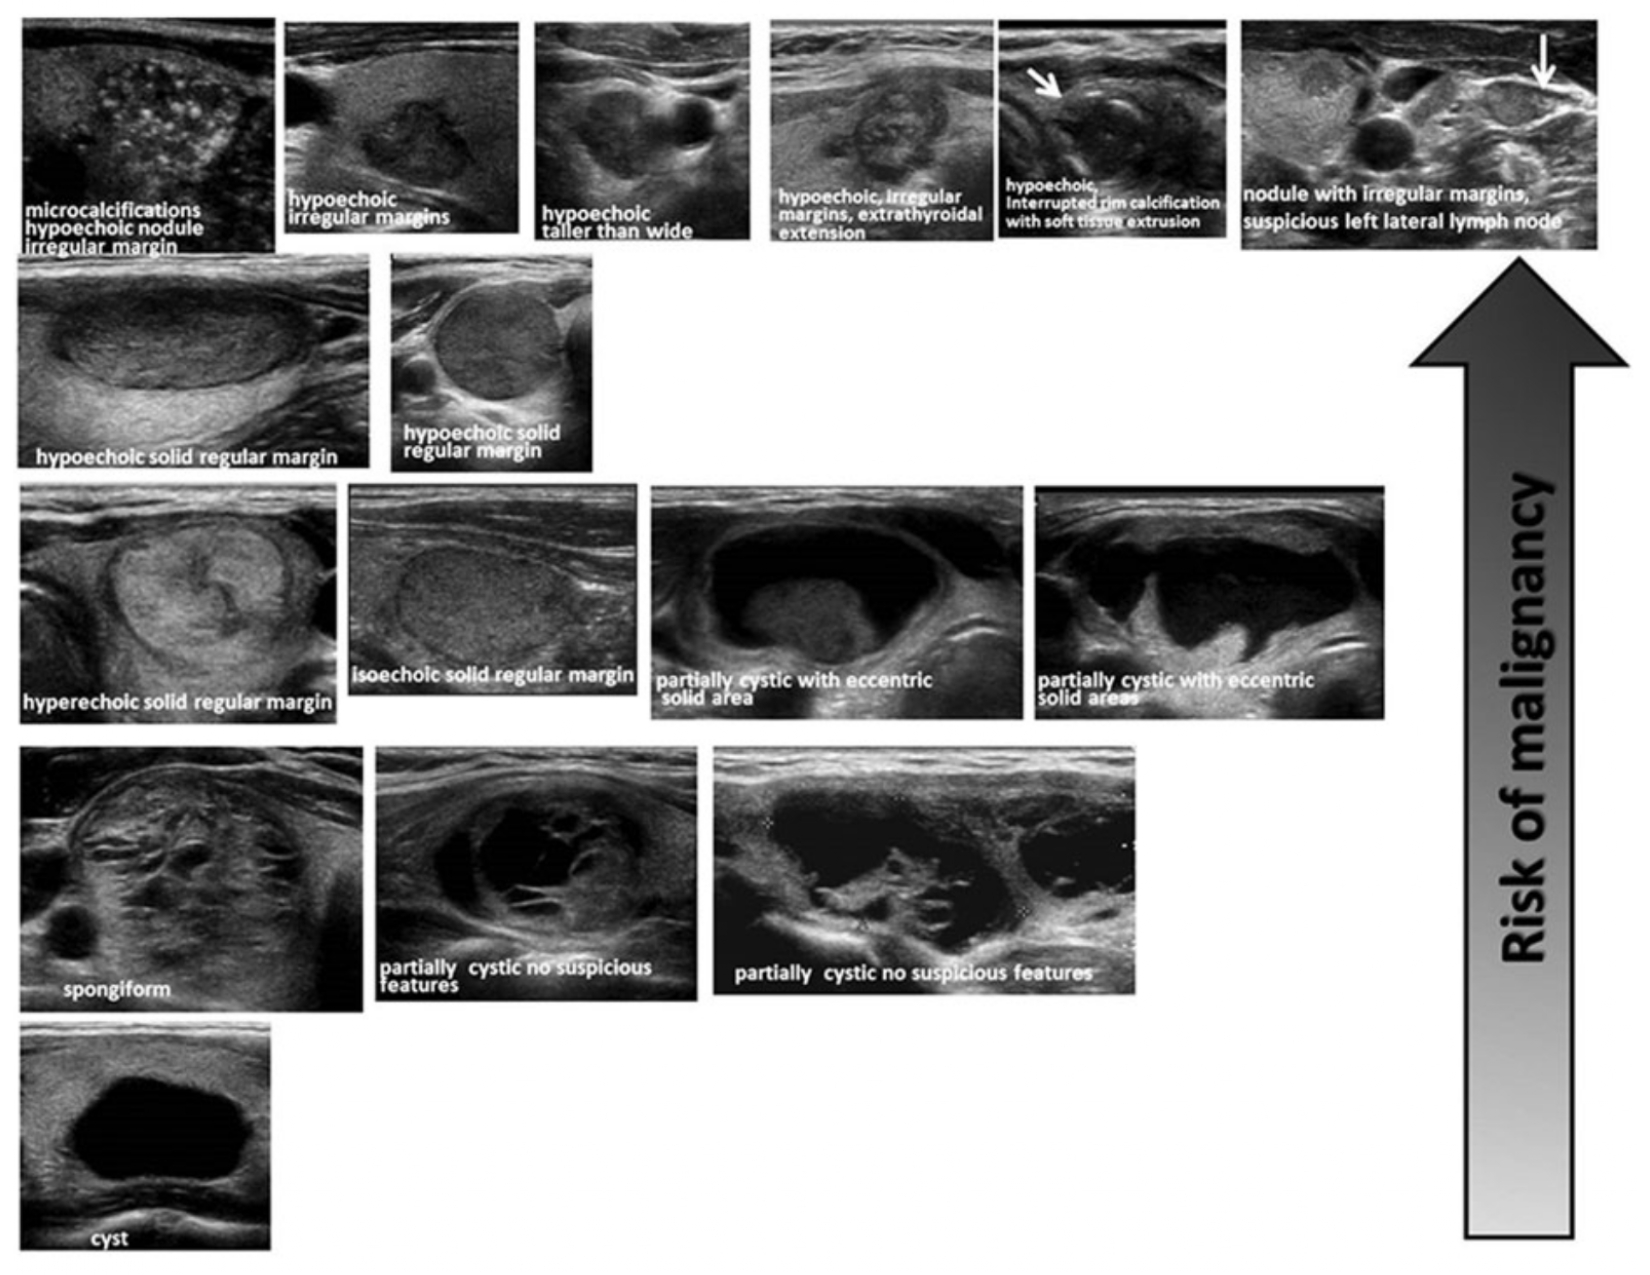

Guidelines have been published based on extensive research comparing surgical pathology results of thyroid nodules to their pre-operative appearance on ultrasound.

- Helps to guide decision making on:

- Which nodules should be biopsied (aka FNA – fine needle aspiration)?

- Which nodules do not need a biopsy but need ultrasound surveillance? And for how long?

- Which nodules can be safely followed with physical exams alone?